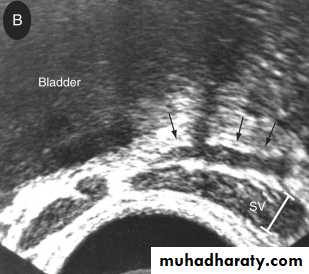

3.Transrectal U.S.(T.R.U.S.)

To assess the prostate,seminal vesicles,ejaculatory duct &vas.Indicated in azospermia with suspected ejaculatory duct obstruction.

Equivocal TRUS findings in suspected ejaculatory duct obstruction can be confirmed by seminal vesicle aspiration.